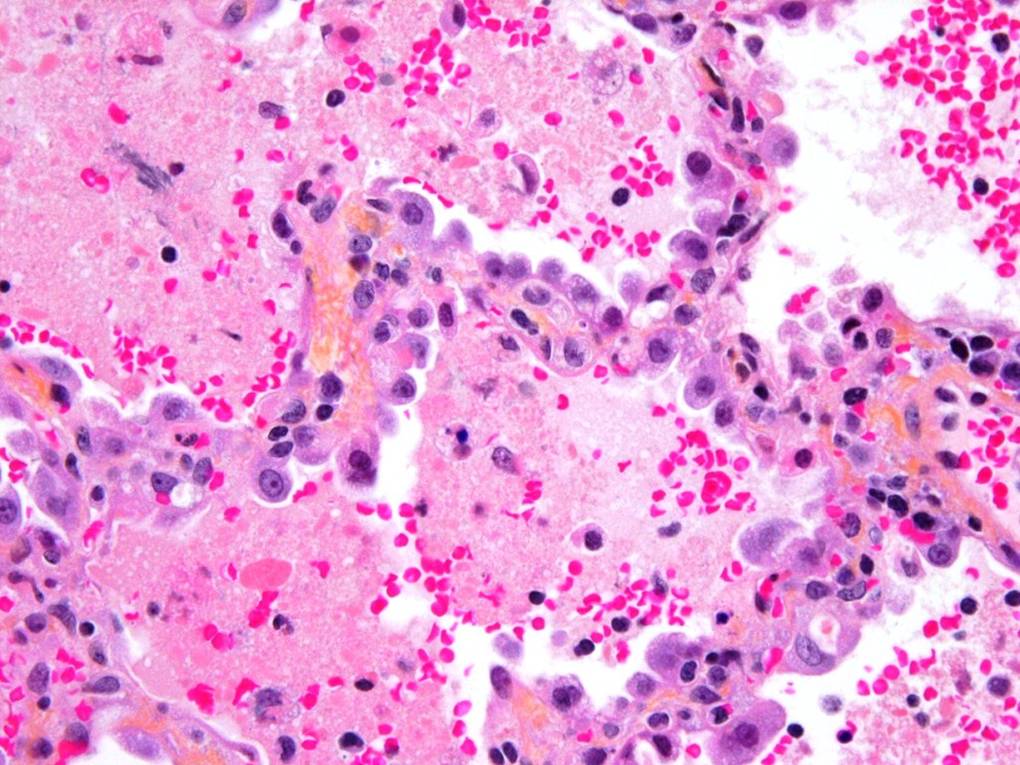

A lung biopsy was performed 24 hours after the steroids were commenced. The biopsy of the right middle lobe and right lower lobe was performed via a right thoracostomy. It was tolerated well with no air leak and no chest tube was required.

Please interpret the histology slides: (The final slide is a Periodic acid Schiff stain (PAS))

| figure 3 | figure 4 | figure 5 |